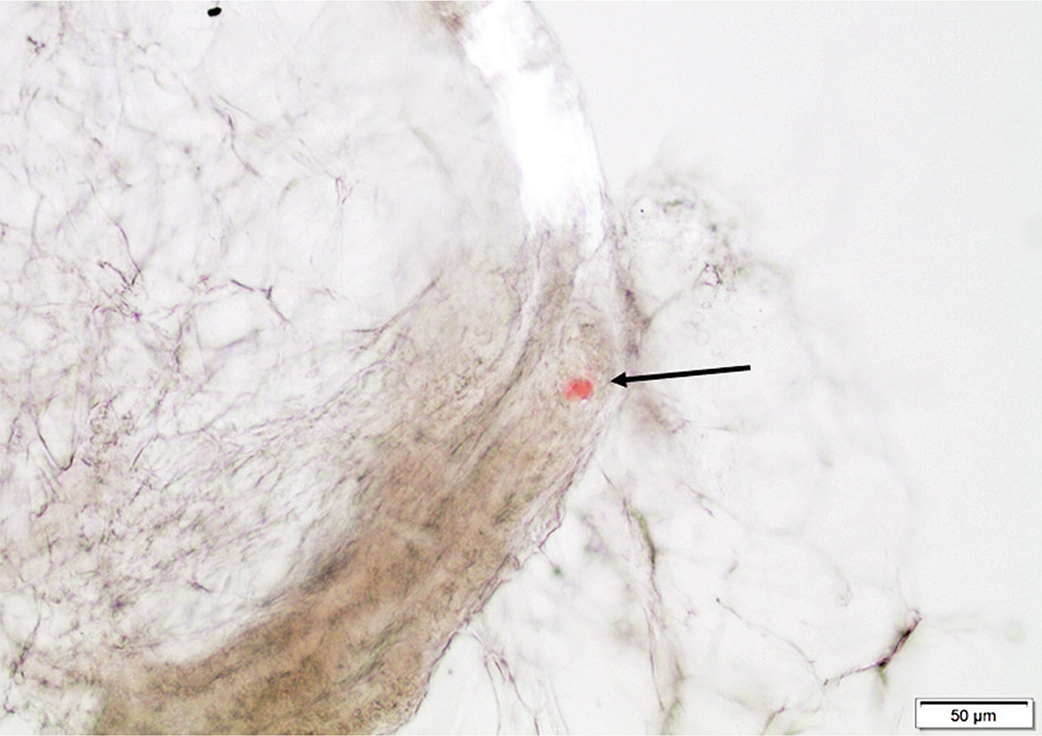

While fine needle aspiration biopsy of subcutaneous fat tissue is an excellent method to diagnose AA and AL amyloidosis, it is less successful for the ATTR forms, particularly wild-type (wt). One reason is that the amount of ATTR amyloid in fat tissue is often sparse. However, an even more important explanation for the results with fine needle aspiration is that the ATTR deposits are associated with collagen that is not easily included in the aspirated material. For this reason, we have largely discontinued the use of fine needle aspiration biopsy from subcutaneous tissue for amyloidosis diagnosis. We now recommend a slightly more invasive method for this tissue. We first introduced a small surgical biopsy (about 1 cm3) (17). Further development has been the introduction of punch biopsies, including subcutaneous tissue (18). Demonstration of small amyloid deposits in sections of fat tissue is often difficult. We, therefore, introduced squeeze preparations of unfixed tissue, which has made the identification of deposits much more successful (19, 20). One further advantage of this method is that some types of amyloid, e.g. ATTRwt, stain better with Congo red when not going through formalin fixation and paraffin embedding steps. Minimal amyloid deposits can be identified in squeeze preparations (Figure 1).

Figure 1. Abdominal fat tissue fragment in a squeeze preparation containing a very small ATTR particle (arrow), stained with Congo red. Bar = 50 μm.